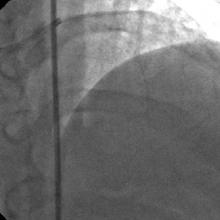

The left system was engaged with XB 3.5 guiding catheter through the femoral route. With the help of a 1.1x1.5mm CTO balloon, we directed a Shinobi guidewire towards the ostial LAD lesion (Figure 4). After making sure that the guidewire was pointing towards the CTO with its tip at the CTO lesion, we used the torquer to gently twirl the guidewire without forcing or overly manipulating it and allowed the guidewire to find its own way through the CTO by patiently twirling it at the lesion site. Within a few minutes, the guidewire jumped through the CTO lesion (Figure 5) and then through the lesion with the help of the CTO balloon (Figure 6). The path was first confirmed by engaging the RCA from the radial approach and injecting dye into the RCA (Figure 7). The CTO was then predilated with a 2.0x30mm Sapphire balloon (Figure 8 and Figure 9) and stented it with a 3.0x36mm DES (Figure 10 and Figure 11). Later the RCA was engaged with a JR 3.5 guiding catheter. A Cougar guidewire crossed the RCA lesion that was directly stented with a 3.0x13mm BMS (Figure 12 and Figure 13).